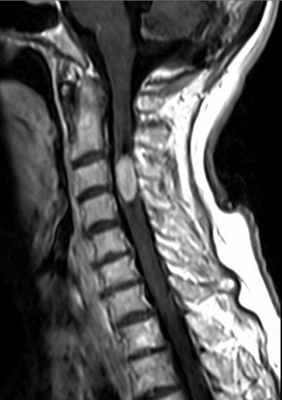

Эпендимома – вторая после астроцитомы по частоте интрамедуллярная опухоль. Спинальную локализацию имеет треть эпендимом, 2/3 приходится на желудочки головного мозга. Опухоль встречается в любом возрасте, однако пик приходится на средний. Чаще развивается у мужчин. Типичная локализация у взрослых – область конского хвоста и конечной нити, эти эпендимомы относятся к миксопапиллярному подтипу. У детей эпендимомы имеют шейную и шейно-краниальную локализацию. Эпендимомы растут медленно по длиннику спинного мозга, вызывая со временем эрозию ножек и задних отрезков тел позвонков. В аксиальной плоскости расположены центрально, симметрично занимая поперечник спинного мозга. Реактивные кисты наблюдаются в 50% случаев, чаще, чем при астроцитомах.

Также как и астроцитома, эпендимома гипоинтенсивна на Т1-взвешенных МРТ и гиперинтенсивна на Т2-взвешенных МРТ. Однако чаще встречается кровоизлияния, причем обычно по полюсам узла. После контрастирования узел виден как четко очерченный (за счет капсулы) и однородный.

МРТ шейного отдела позвоночника. Эпендимома шейного отдела спинного мозга. Сагиттальная Т1-взвешенная МРТ после контрастирования.